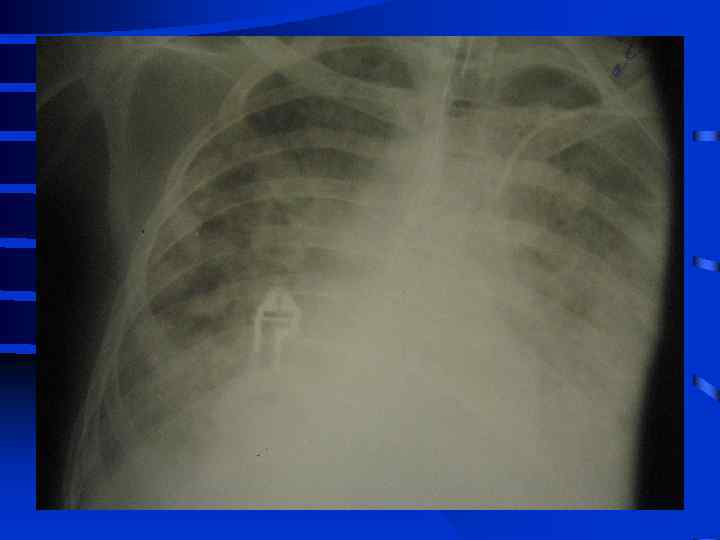

• I стадия Все изменения носят умеренный характер, индекс оксигенации (Pa. O 2/Fi. O 2) более 300, Pa. CO 2 снижен до 34 - 32 мм. рт. ст. , рентгенографически полнокровие легких, ячеистая деформация на фоне усиленного легочного рисунка. • II стадия Повторное, часто резкое ухудшение состояния. Психические нарушения (беспокойство, неадекватность), тахикардия свыше 110 - 120 в мин. , АД сист. более 150 мм. рт. ст. , индекс оксигенации менее 250 - 200, артериальная гипокапния. Рентгенографически - появление мелкоочаговых теней на периферии

• III стадия необходима респираторная поддержка, сознание нарушено, индекс оксигенации менее 200, шунтирование 30 - 50% от величины МОК. Появляются признаки полиорганного поражения: нарушение функции кишечника (парезы, острые язвы) • и почек (эпизоды олигурии) • Рентгенографически - сливные тени, иногда первые признаки гидроторакса

• IV стадия появляются симптомы присоединения инфекции с развитием гнойного трахеобронхита и пневмонии (госпитальной), признаки сепсиса, вторая волна полиорганной недостаточности. Индекс оксигенации менее 100, появляется гиперкапния. Рентгенографически - резкое снижение прозрачности легочных полей, множественные хлопьевидные тени (“снежная буря”).

Объективные признаки развития ОРДС • 1. Индекс оксигенации снижен • 2. Симметричные рентгенографические изменения инфильтративного характера • 3. Увеличение внутрилегочного шунта (более 25% от величины МОК) • 4. Возрастание альвеолярно-артериальной разницы по кислороду (более 250 мм. рт. ст. при Fi. O 2 = 1, 0) • 5. Легочная гипотензия (PCWP не более 12 мм. рт. ст. ) • 6. Уменьшение растяжимости (податливости) легких 50 мл/см. вод. ст. и менее

Тяжесть ОРДС по J. Murray (1988) • А) Рентгенография (инфильтрация от 0 до 4 квадрантов = 0 - 4 балла • Б) Гипоксия (PAO 2/Fi. O 2) от 300 и выше до 100 и менее = 0 - 4 балла • В) Растяжимость легких (от 80 и более до 20 и менее мл/см. вод. ст. ) = 0 - 4 балла • Г) ПДКВ при ИВЛ (от 0 до 14 см. вод. ст. и выше) = 0 - 4 балла • К от 0, 1 до 2, 5 - умеренное повреждение, более 2, 5 - тяжелое